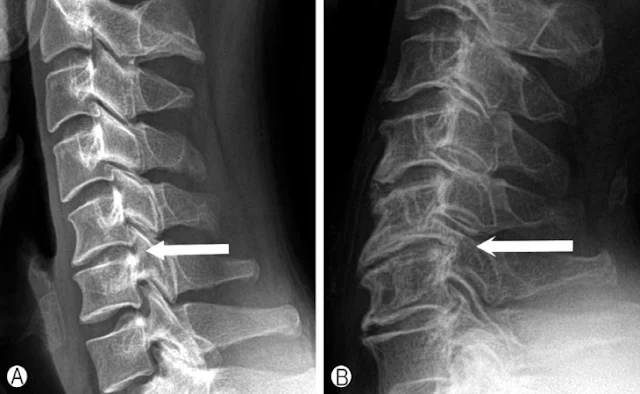

목디스크 환자분들이 통증을 느끼는 부위는 대부분 디스크 퇴행이 많이 진행된 부위입니다.

이 부위는 다른 부위보다 더 많이 움직이게 되고, 그만큼 더 약해진 상태예요.

그런데 우리가 잘못된 스트레칭을 반복하면 어떻게 될까요?

더 약한 부위를 계속해서 자극하게 되고, 결국 통증은 반복됩니다.

- 퇴행된 디스크 → 불안정해진 관절

- 반복되는 목 움직임 → 더 많은 염증 유발